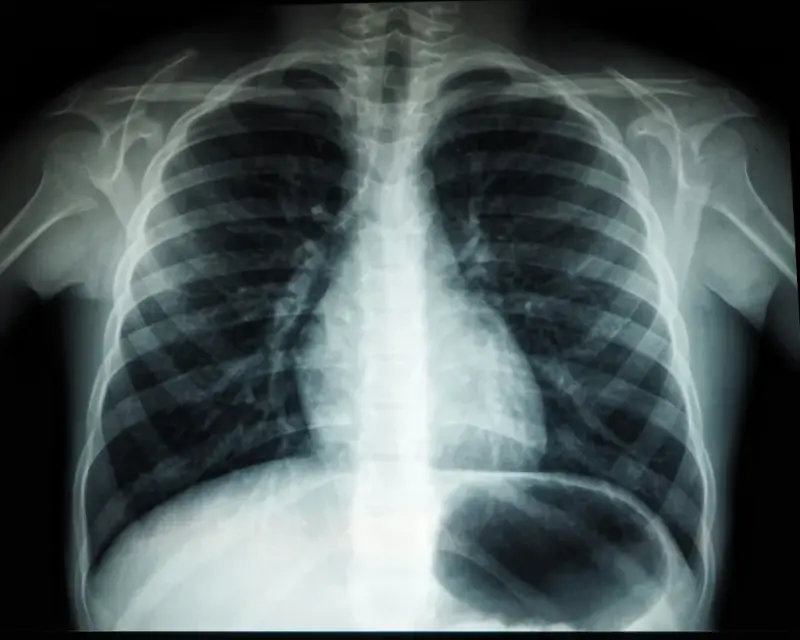

Badania obrazowe stanowią podstawę w diagnostyce wielu schorzeń. Podstawową przeszkodą w ich przeprowadzeniu jest brak wykwalifikowanego personelu, który szczegółowo opisze wyniki. Z pomocą przychodzi teleradiologia, która może znacząco usprawnić całą procedurę diagnostyczną. Czym dokładnie jest i na jakich zasadach funkcjonuje?

Teleradiologia to usługa polegająca na zdalnym opisie badań obrazowych – tomografii komputerowej oraz rezonansu magnetycznego. Mogą być one wykonane w dowolnym miejscu – przychodni, szpitalu czy ośrodku zdrowia, a następnie są przekazywane w formie zapisu komputerowego do firmy specjalizującej się w teleradiologii. Metoda ta pozwala znacząco ograniczyć czas potrzebny na wykonanie opisu, a tym samym przyspieszyć całą procedurę diagnostyczną. Więcej na jej temat można dowiedzieć się na stronie https://telediag.pl/. Jest to witryna firmy, która świadczy usługi teleradiologiczne dla jednostek z całego kraju.

Z usług teleradiologii coraz częściej korzystają zarówno prywatne, jak i publiczne ośrodki zdrowia. Jest to rozwiązanie przede wszystkim dla tych przychodni czy szpitali, w których zatrudnionych jest niewielu lekarzy radiologów albo którym trudno znaleźć jakiegokolwiek specjalistę. W wielu przypadkach pełna diagnostyka bez wykonania badania obrazowego jest niemożliwa, jednak na jego opis trzeba czekać nawet kilka tygodni. Znacząco wpływa to na stan zdrowia pacjenta, który w każdym momencie może się pogorszyć. Teleradiologia to sprawdzony sposób na szybki opis badania. Sama procedura opisywania nie różni się od tej, która odbywa się w ośrodkach zdrowia, w których zatrudnieni są radiolodzy. Lekarz otrzymuje zdjęcia, które następnie ocenia i opisuje. Wszelkie dane przesyłane są zdalnie, dlatego czas oczekiwania na wynik zostaje skrócony do minimum.

Teleradiologia zyskała popularność w czasach, gdy coraz więcej pacjentów korzysta z porad lekarskich online. Opis badań obrazowych na odległość również nie stanowi żadnego problemu, a wręcz przeciwnie – może rozwiązać wiele problemów, z którymi borykają się szpitale i przychodnie. W wielu miejscach w ogóle nie ma możliwości wykonania badań obrazowych, jednak problemem nie jest brak sprzętu, a lekarza, który opisałby wyniki. Niestety, tomografia komputerowa czy rezonans magnetyczny, pomimo dużej wartości diagnostycznej, nie są przydatne lekarzowi specjaliście, jeśli nie posiadają stosownego opisu. Sporządzenie go leży w kompetencji radiologa, który może świadczyć usługi zdalnie. Teleradiologia pozwala zoptymalizować koszty działalności podmiotów leczniczych i do minimum skrócić czas oczekiwania na wyniki. Jest to korzystne zarówno dla pacjenta, jak i dla lekarza prowadzącego diagnostykę. Wyniki opisywane są w trybie planowym – jednostka zlecająca otrzymuje je w ciągu 5 dni, podczas gdy wynik opisywany tradycyjną metodą często dostępny jest dopiero po 2 tygodniach. Teleradiologia bazuje na systemach komputerowych, które są zabezpieczone w odpowiedni sposób. Nie trzeba więc obawiać się wycieku danych czy jakichkolwiek awarii, które mogłyby zakłócić pracę. Z tej usługi korzysta już wiele ośrodków medycznych, zwłaszcza z mniejszych miejscowości. Niemniej jednak jest ona stosunkowo nowa na rynku, dlatego w przyszłości prawdopodobnie większość przychodni i szpitali przejdzie na tryb zdalny opisu badań radiologicznych, mając na uwadze wynikające z niego korzyści.